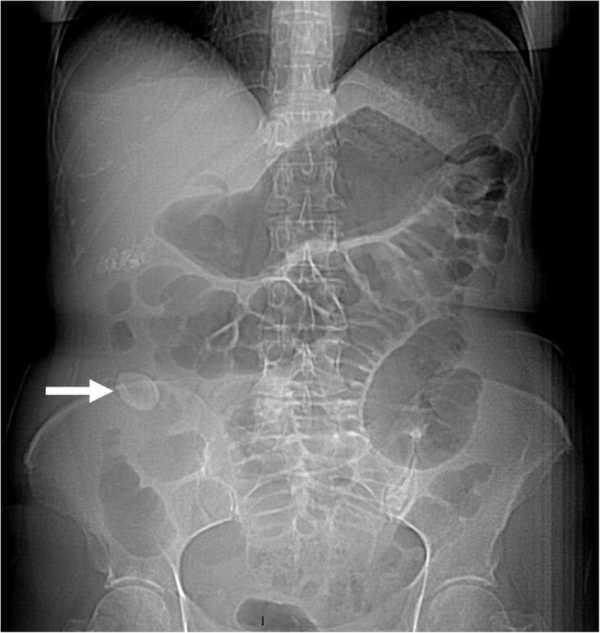

24. Обструкция кишечника: рвота (с желчью или фекалиями), боли и колики, запор. Тяжесть симптомов зависит от места и причины обструкции.

- Рентгенография ЖКТ с применением контрастной жидкости для выявления пораженных участков.